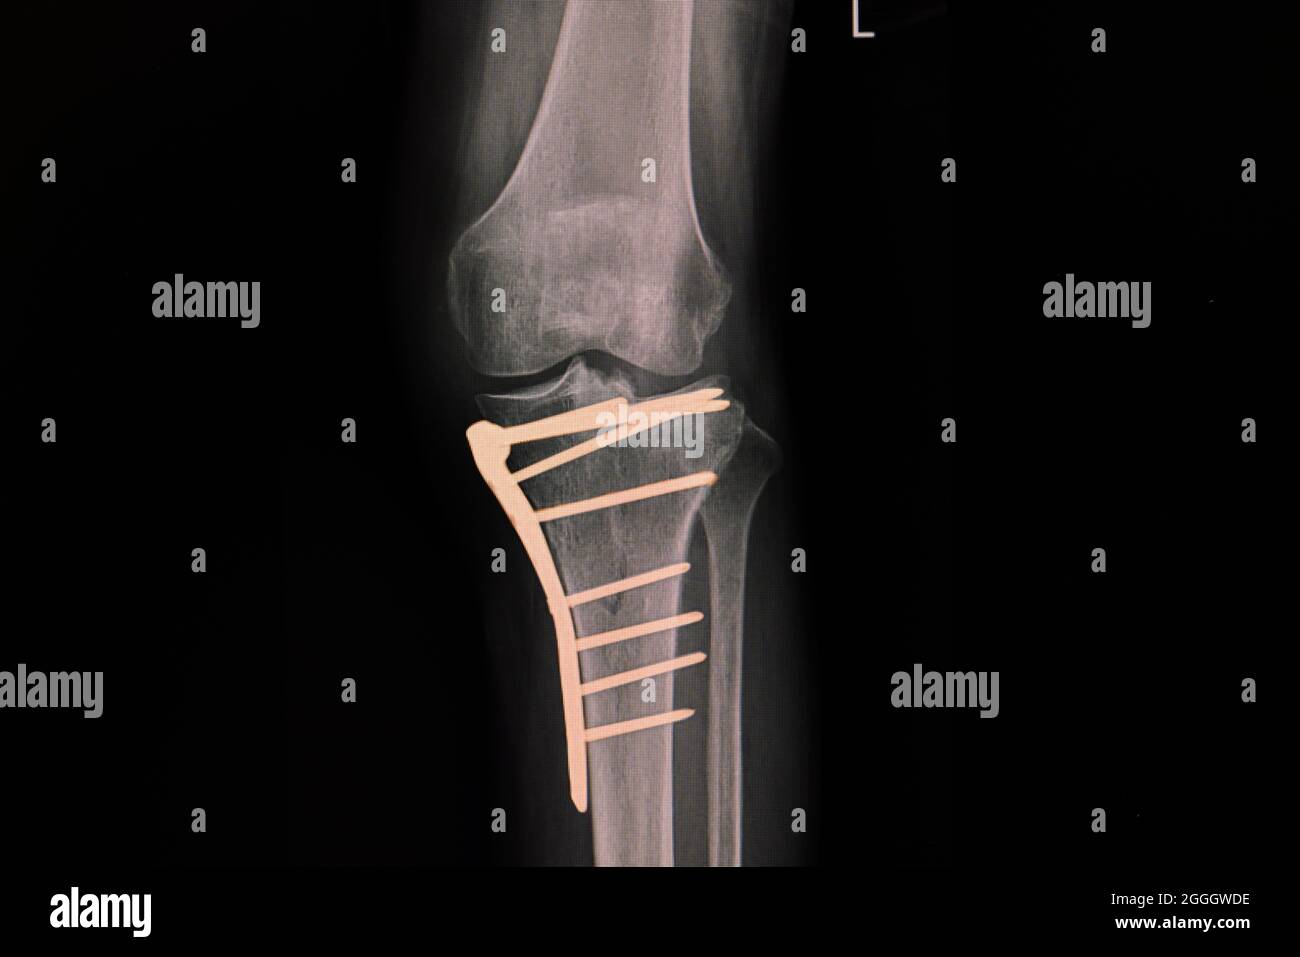

Source: joipoinme.pages.dev Röntgenfilm eines Knies eines Patienten mit gebrochener proximaler Tibia nach der Fixierung von , Eine mögliche Ursache für Fußschmerzen sind Schrauben, die im Rahmen einer Osteosynthese eingesetzt wurden Diese Prozedur erfordert meistens einen speziellen chirurgischen Eingriff, der im Vergleich zur Osteosynthese relativ kurz ist.

Platten, Schrauben, Mark- nägel sowie innere und äußere Festhalter werden dazu verwendet, die Knochen beim Zusammen- wachsen zu stabilisieren Schmerzen im Fuß können sehr unangenehm sein und verschiedene Ursachen haben

Platte Und Schrauben Im Fuß Entfernen . Trockene Haut am Fuß entfernen Stock Photo 11105594 Bildagentur PantherMedia Einige Patienten berichten auch von wetterbedingten Schmerzen im Fuss oder Knöchel. Osteosynthesematerial wie Schrauben und Platten werden verwendet, um Knochenbrüche zu stabilisieren und die Heilung zu unterstützen.